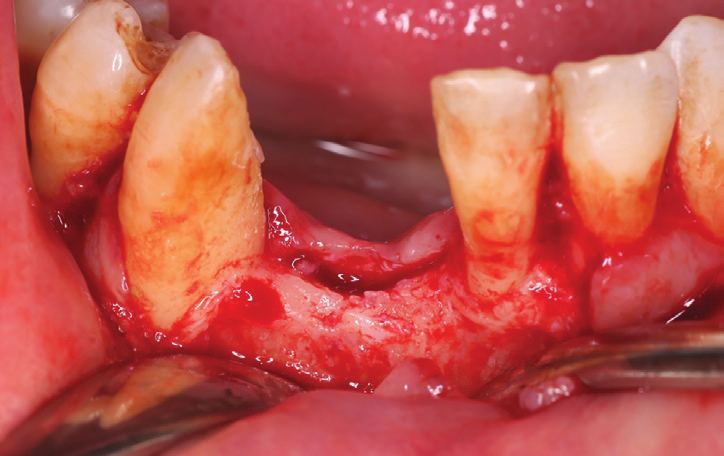

Figure 2: Intraoral view showing the extended bone and gingival loss with recession on both central incisor and canine.

Figure 3: Occlusal intraoral view showing the advanced amount of bone loss.

After removal of the bridge an extended bone loss was found. (Fig.2, 3). X-rays and CAT views were taken for the region. The amount of bone loss was extended which was an indication for autologous bone graft. A PRF associated bovine bone technique was planned. A linear incision with mucoperiosteal flap elevation was conducted. The adjacent teeth showed also bone loss (Fig.4).